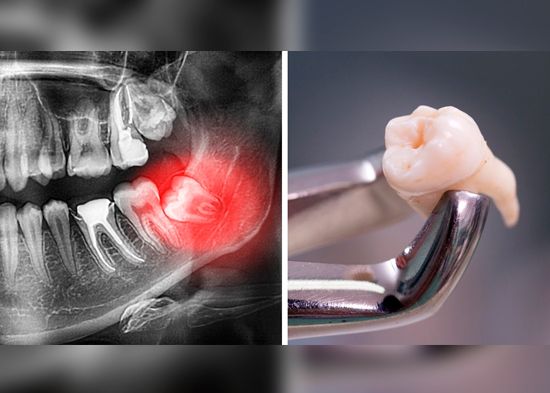

Muelas del juicio retenidas: 3 problemas que pueden ocasionar si no las retiras a tiempo

El dolor que causan las muelas del juicio puede ser uno de los más intensos, sobre todo cuando no cuentan con el suficiente espacio para emerger, causando malestar en garganta, oído, cabeza, mandíbula, encías inflamadas, enrojecidas, sensibles y mal aliento. Aunque puede ser temporal, ¿qué pasa cuando están retenidas? 3 problemas que pueden ocasionar si no las retiras a tiempo.